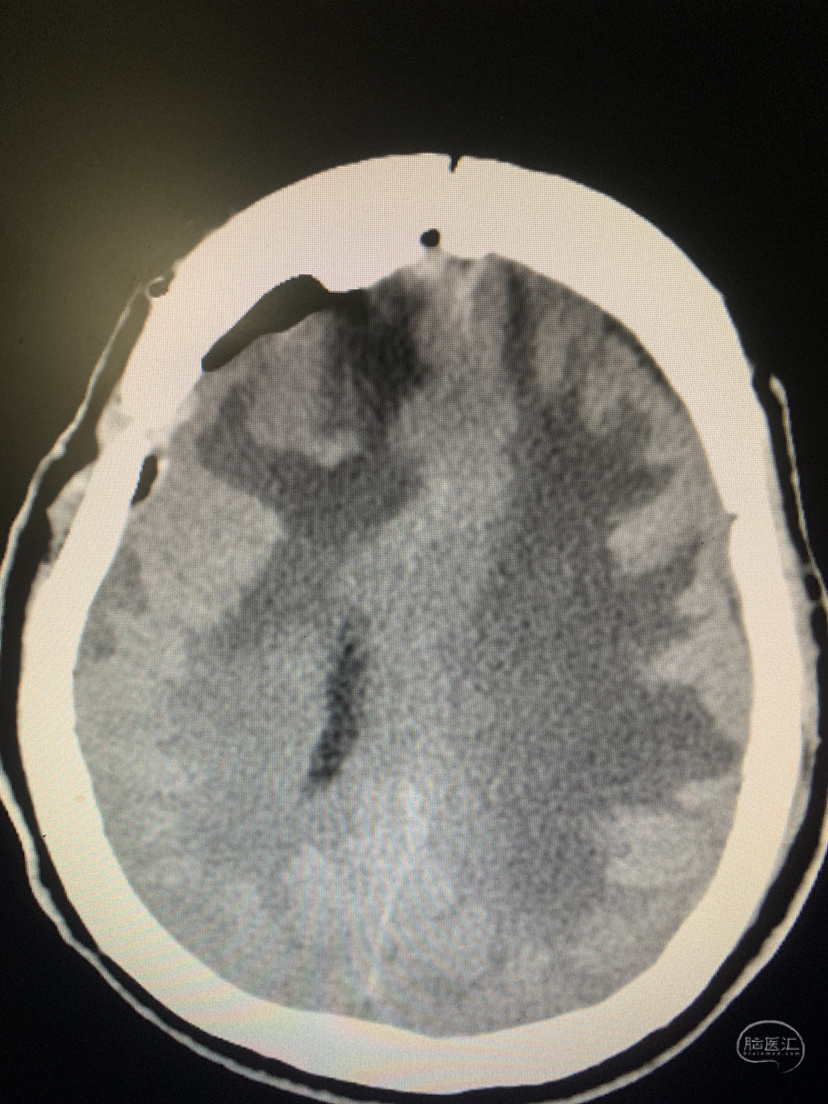

术前术后对比

术后CT